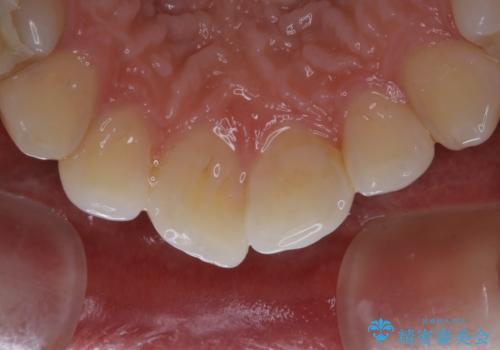

- 歯医者でのクリーニングはかなり久しぶりで、今後虫歯の治療もしていくので綺麗にしたいとのことでした。PMTC30分コースを行いました。

PMTCを行う際には担当の歯科衛生士が、患者様1人1人の虫歯・歯周病などのリスク・ブラッシングスキルなどを確認します。

日々の磨き残しや唾液の成分などによりバイオフィルムや歯石はどうしても付着してしまいます。歯石や汚れを放置していると、そこで病原菌が繁殖す始めます。歯肉に炎症が生じると歯周病などの引き金となります。